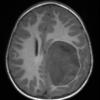

ETMR - Embryonal Tumor Multilayered Rosettes (9)